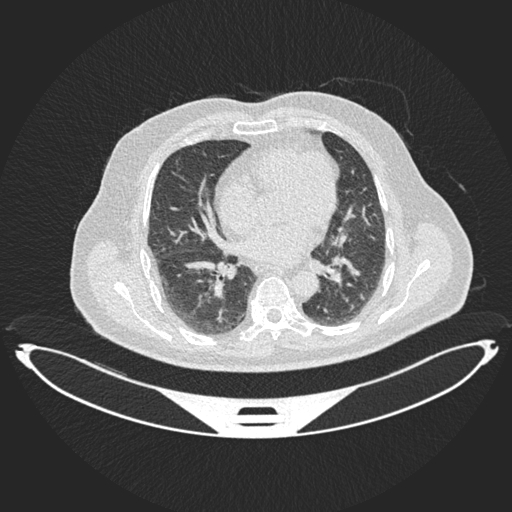

Analyzed Image

b.jpg

Uploaded: 2025-08-03 04:59:10Best Model Result

Malignant

Confidence: 65.9%

Model: DenseNet121

Ensemble Prediction

Confidence: 52.4%

Average of all modelsModel Predictions Comparison

ResNet50

Malignant:

Normal:

ConfidenceDenseNet121

ConfidenceEnhancedCNN